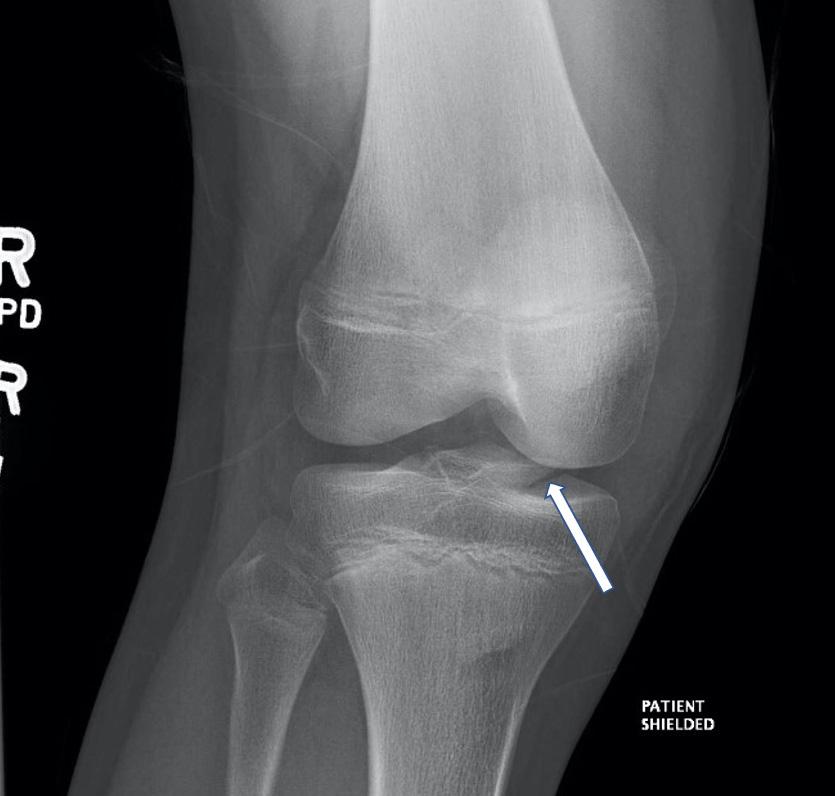

Case Series: In this case series we discuss three patients who presented with bilateral frostbite on the plantar surfaces. Ultrasound-guided PTN blocks were performed on these patients and pain control was achieved in under 10 minutes, facilitating burn care. No patient experienced adverse effects. All patients had been scheduled for future debridement that was either not performed or performed using intravenous (IV) medications due to pain control issues.

DISCUSSION

This case series demonstrates the severity of frostbite pain and the challenge it creates to receiving appropriate wound care. Ultrasound-guided PTN blocks bypass this challenge and achieve effective analgesia in the ED, allowing for optimal wound debridement as shown in these patients’ experiences.

There are multiple strengths and limitations in our approach. The most clinically relevant benefit of the PTN block is the analgesia it provides. Pain is a significant barrier to treating frostbite injuries, originating from the burn itself as well as from rewarming and debridement.2,9 All patients reported pain scores of 7/10 to 10/10 with PO medications only. Following the PTN block, patients reported drastic improvement in their pain levels and tolerated debridement without additional medications. This outcome aligns with prior studies that have shown pain control success rates of 95-100% when using the PTN block for foot surgeries.7,8 Later attempts at repeat debridement were either unsuccessful or performed under procedural sedation for patient one and patient two, highlighting the superiority of the PTN block analgesia.

The addition of ultrasound guidance further improved the PTN block. Peripheral nerve blocks performed with ultrasound provide better pain control, require fewer additional pain medications, and have fewer complications as compared to landmark guidance.4,12,13 A study by Kakhi et al revealed shorter time to onset and longer duration of analgesia with ultrasound guidance.13 Shah et al demonstrated the superior accuracy of ultrasound for targeting the posterior tibial nerve and avoiding surrounding structures.14 This accuracy translates into increased block success and fewer incidents of intravascular injection and systemic toxicity.4,13,14 Each of our patients reported significant pain relief that was achieved in less than 10 minutes, and no patient experienced adverse effects.

Our experience using the PTN block for these patients demonstrates the accessibility and relevance of this block for future patient encounters. The PTN block is a well described and thoroughly examined nerve block that is accessible to clinicians of different training levels and experience.7,8,15 In the series we report, it was performed by first- and third-year emergency medicine residents under the guidance of an ultrasound-trained faculty member. Emergency departments in colder climates frequently see frostbite as a chief complaint, and this case series can help guide the use of PTN blocks for pain control in such patients.

Despite the accessibility of the PTN block, clinician comfort with nerve blocks and the availability of ultrasoundtrained faculty could limit its use. The ultrasound-guided block is also more time intensive when compared to PO or IV pain medications.4 Lastly, our case series only focuses on the experiences of three patients with second-degree frostbite of bilateral plantar surfaces. Patients with other levels and locations of frostbite injury may have different outcomes.

CONCLUSION

This case series demonstrates that the ultrasound-guided PTN block provides superior pain relief, has low risk of systemic toxicity, allows for necessary wound care, and is accessible to clinicians of varying training levels. Ultrasoundguided PTN blocks have the potential to play a major role within a multi-modal pain control strategy for frostbite management. This role is unequivocally applicable within the

emergency department. The ease and accessibility of the block also lends its use to other clinical contexts, including outpatient wound clinics and inpatient burn units. These potential applications of the PTN block warrant further research on its use for frostbite management in different clinical scenarios.